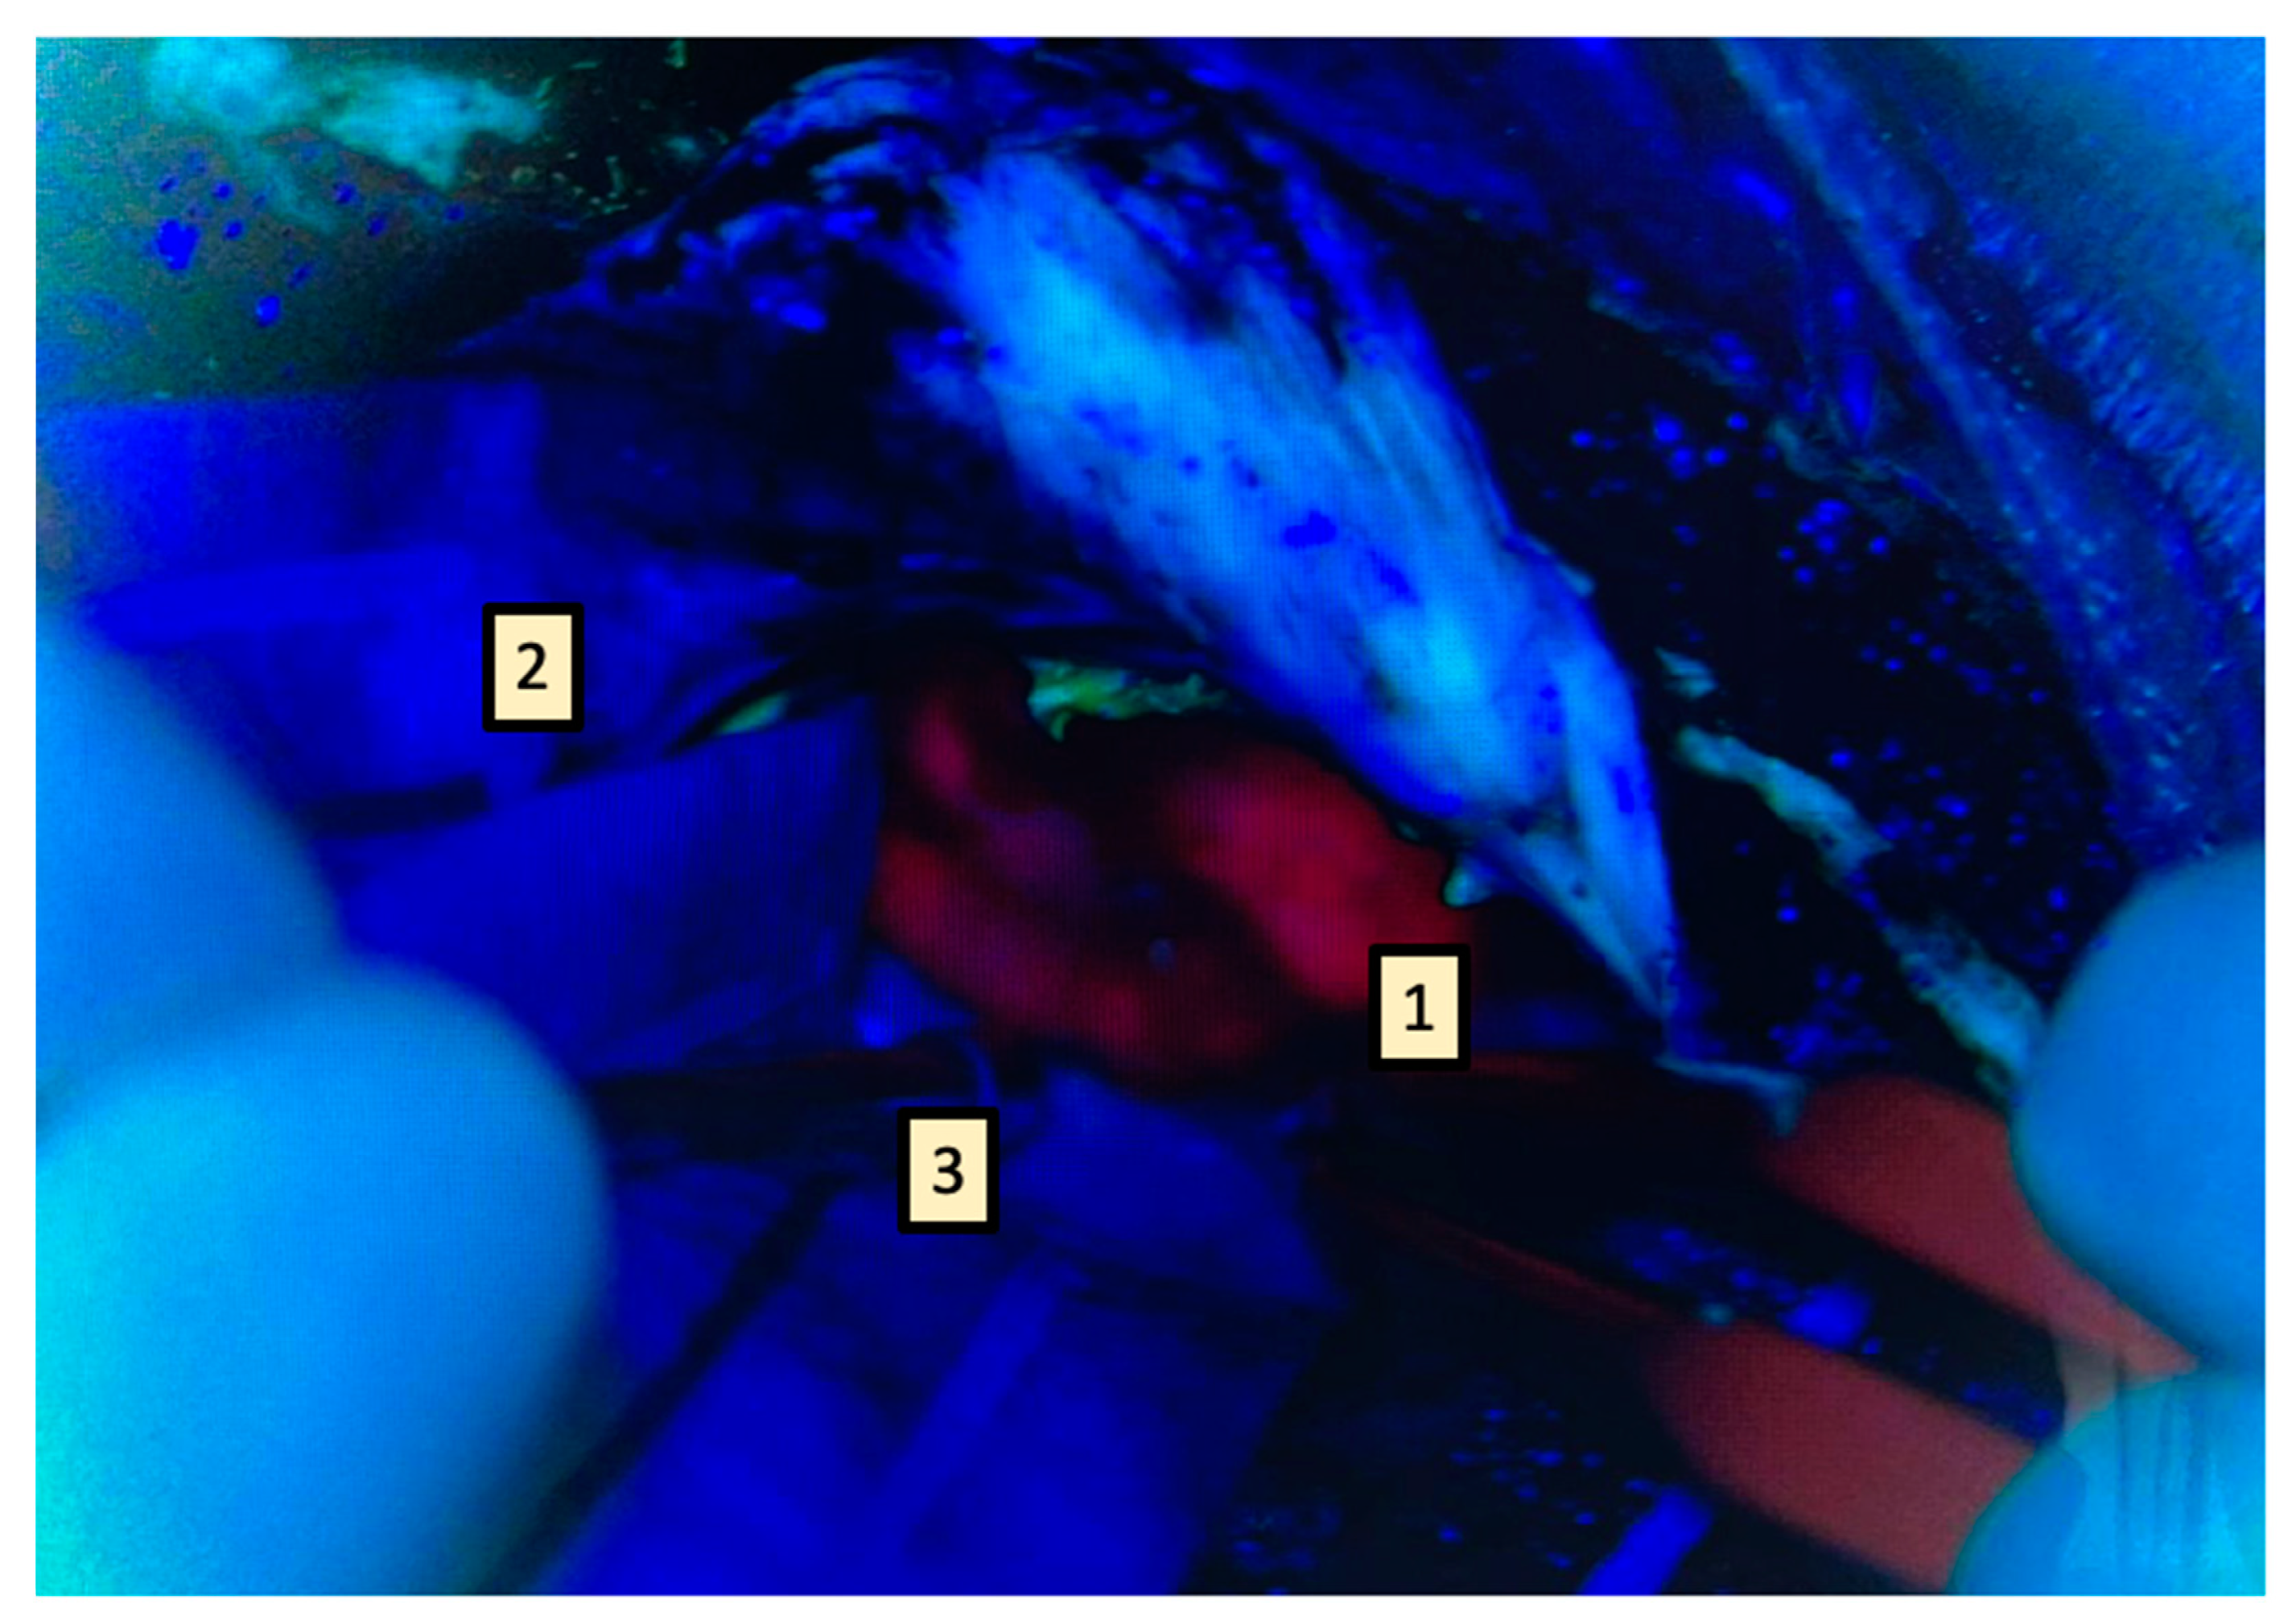

First, hemostasis should be carefully managed before checking the surgical cavity edges; hemostatics can hinder fluorescence, therefore they should be removed before inspection. Second, an aspirator should always be left in a safe position over a cottonoid, close to the area of inspection and before switching to blue filter. It is crucial to leave it inside the surgical cavity, otherwise it might be difficult to introduce it in a rather dark environment. Providing suction, the aspirator keeps the field clean during inspection and could be used to “brush” the area of interest, thus maximizing fluorescence visualization. Third, it is helpful to inspect one portion of the cavity at a time and cover the rest with cottonoids; this allows to focus microscope light efficiently rapidly perform a temporary haemo-stasis on a limited area (while the rest of it is controlled by cottonoids) and take ad-vantage of aspiration as explained before. (Figure 3).

Figure 3.

How to avoid hindering fluorescence. First, one portion of the cavity is inspected at a time (1) while the remaining part is covered with cottonoids (2). Hemostasis is performed in the limited (uncovered) area while cottonoids prevent bleeding from the rest of the cavity. The aspirator is introduced before switching to blue filter (this could be difficult to place in dark conditions), which is placed below the area being inspected (3). This keeps the cavity clean and allows the use of the aspirator to brush resection walls.